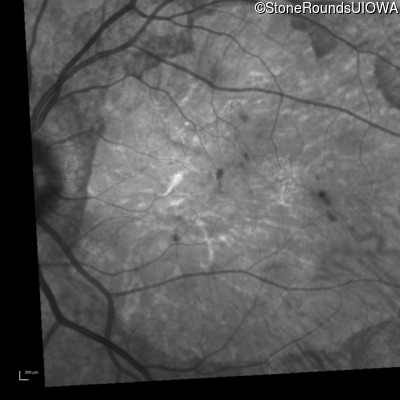

Infrared Fundus Photograph - Right - 10/200 sc

Exemplar

Infrared Fundus Photograph - Left - 10/125 sc